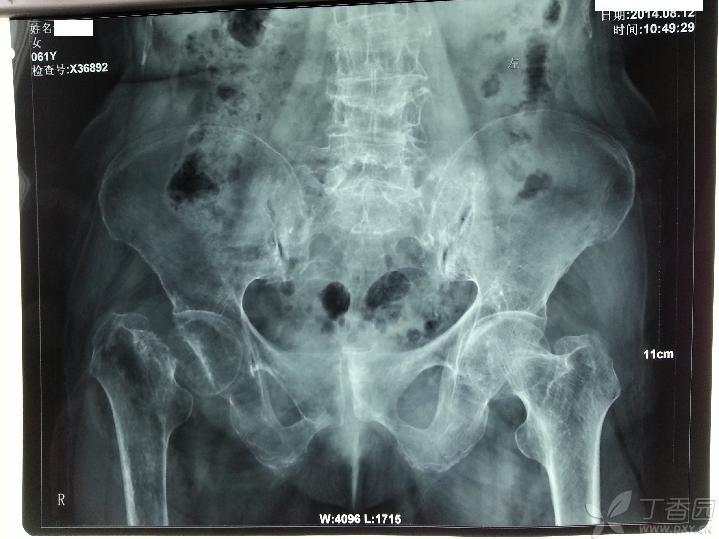

患者62岁女性,无明显外伤史,右髋关节疼痛活动受限1年,加重半年入院,患者一年前无明显诱因出现右髋关节疼痛,活动受限,未到医院诊治,自行以腰椎间盘突出症在家治疗,休息,口服药物治疗,无效,但可以扶拐行走。

查体:心肺腹未见明显异常,右下肢短缩3厘米,右髋关节活动受限,右下肢无明显水肿,无明显感觉异常,膝上10厘米右侧大腿周径较左侧减少约2厘米,右小腿周径较左侧减少约1厘米,末梢血运好好。X片如下,右股骨颈陈旧性骨质,髋臼侧及股骨侧继发骨质疏松。CT检查显示右股骨颈骨质,股骨近端骨质未见明显破坏。

CT测得股骨头直径约46mm,股骨小转子下10厘米髓腔左右径约17-18mm,